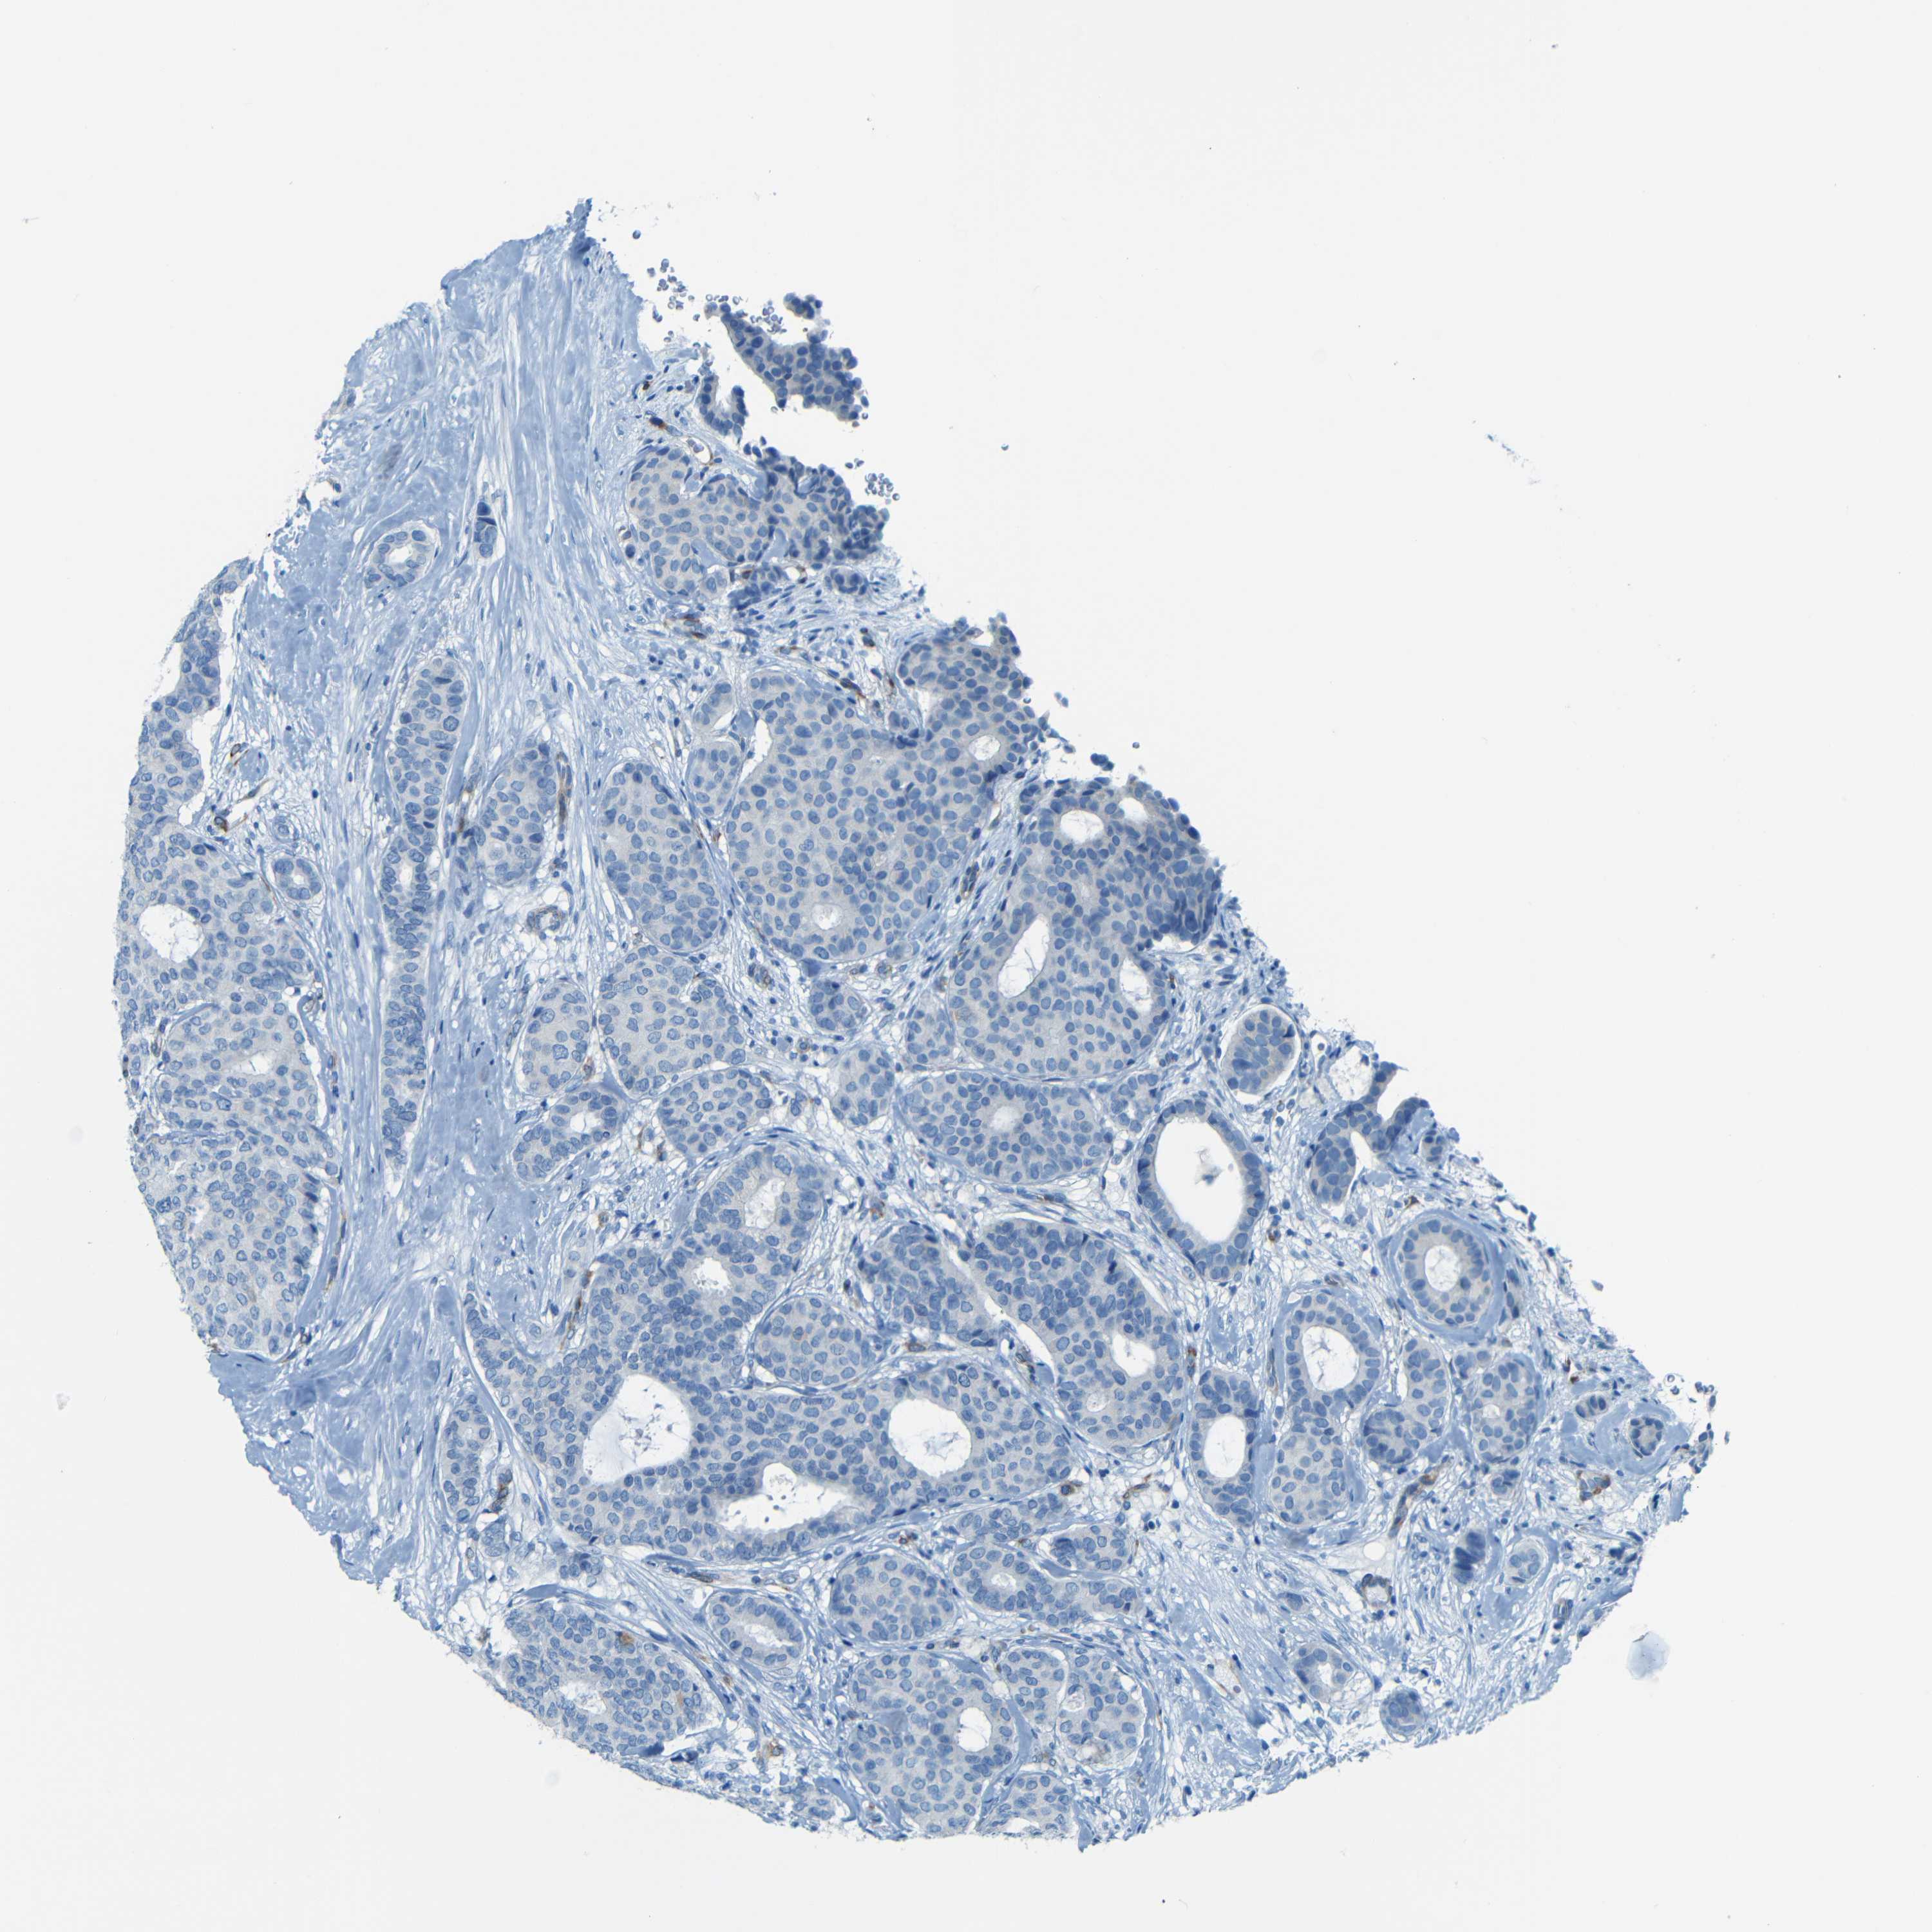

CANCER BREAST CANCER Show tissue menu

Breast cancer

Human cancer